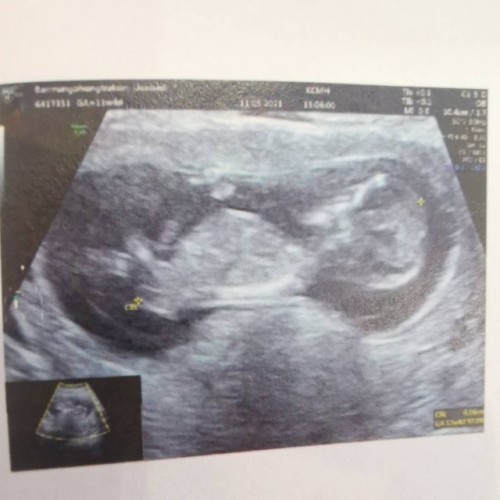

แม่บ้านไหนคลอดเดือน พศฤจิกายน บ้างกี่วีคกันแล้ว

บ้านนี้กำหนดผ่า 2 พฤศจิกายน 2564

12พ.ย. คะ 14+6 w

3 พ.ย 16+1 จ้า

17 พ.ย. ครับ

18พ.ย.ค้ะ 14w

2พ.ย ค่ะ 16w